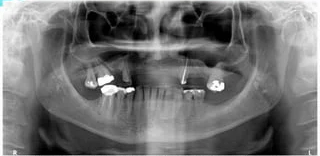

2. What condition can be seen in the following X ray? ( Open arrow)